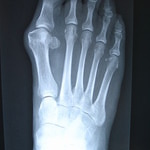

A bunion deformity occurs when the 1st metatarsal bone (the bone behind your big toe that makes up part of the ball of your foot) shifts away and/or upwards from the 2nd metatarsal next to it. This causes a sideways buckling of the joint which results in the big toe bending towards the 2nd toe. While it can appear that a pointed-toe shoe is pushing the big toe over, the true driving force is the shifting of the metatarsal bone.

Treating bunions involves dealing with both the deformity and the cause. When symptomatic, bunions are corrected surgically by shifting the metatarsal back towards where it should be. But afterwards, the faulty mechanics—the instability—must be addressed by the use of prescription orthotics. This deals with WHY the bunion developed in the first place and makes it less likely for the deformity to return after surgery.